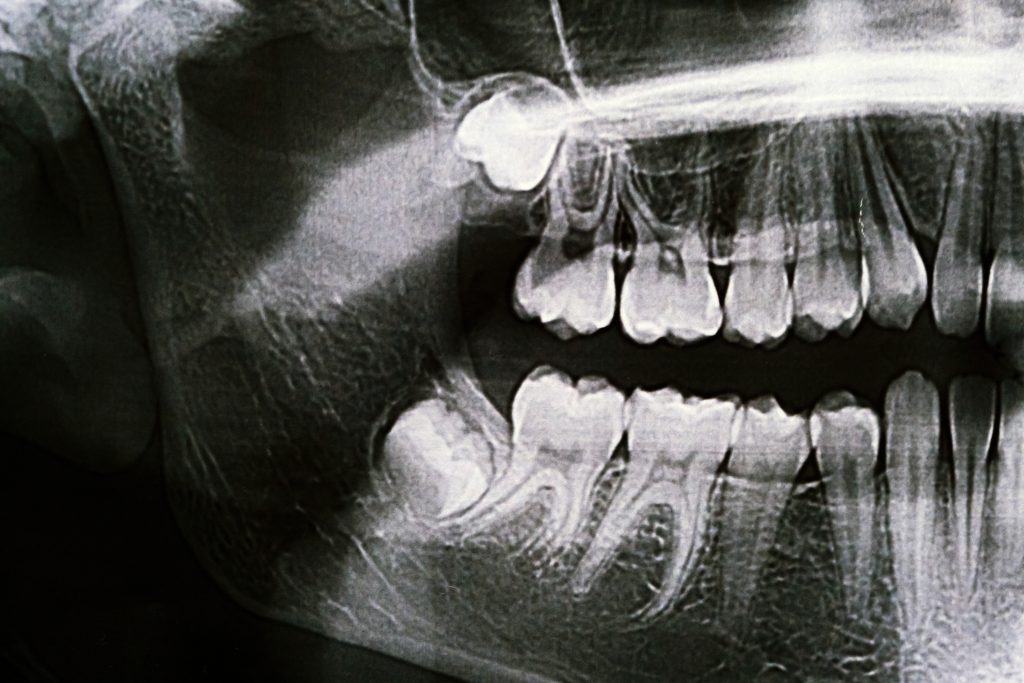

A consultation and special x-ray (panorex) will help us determine whether your wisdom teeth are impacted, if there’s enough space for them to erupt, and how complex removal may be. Wisdom tooth removal is often recommended to prevent complications such as pain, infection, and crowding.